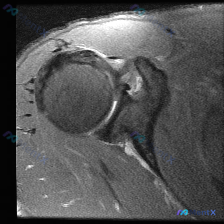

整理到一份肩关节影像病例资料,先放单张轴位T2加权MRI: > 影像基础:肩关节轴位T2加权序列,可见肱骨头、关节盂、肩胛下肌等结构,前下盂唇区域存在局灶性高信号影,肱骨头骨皮质完整,无明显关节积液或巨大占位。 想问问大家,仅根据这张图像的表现,第一反应会先往哪个方向考虑?有没有需要特别注意的鉴别点...

看到这份肩部MRI的读片需求,核心观察点是软组织积液,整理了一下完整的分析思路分享给大家。 一、影像基本信息 这份是肩部MRI轴位T2加权图像,先整理一下所有明确的影像学发现: 1. 骨骼关节:肱骨头和关节盂对位基本正常,没有明显脱位;但关节盂前下部盂唇形态异常,有高信号影,还存在结构连续性中断,盂...